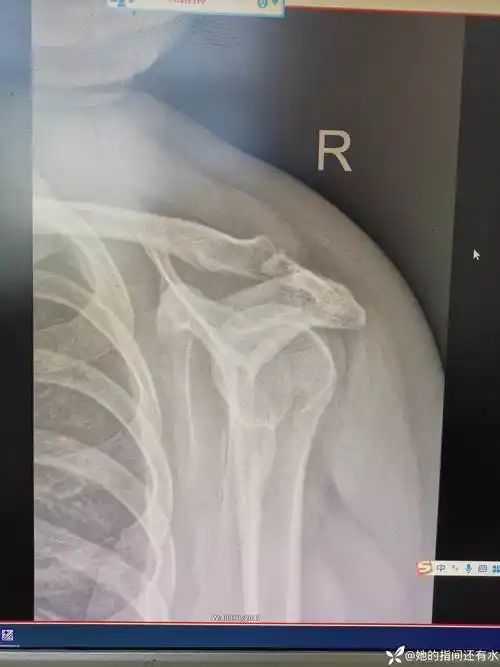

肩关节ap位x线平片显示肱骨头(白箭头)内旋导致的形态变圆("灯泡征").

灯泡征高度提示肩关节后脱位